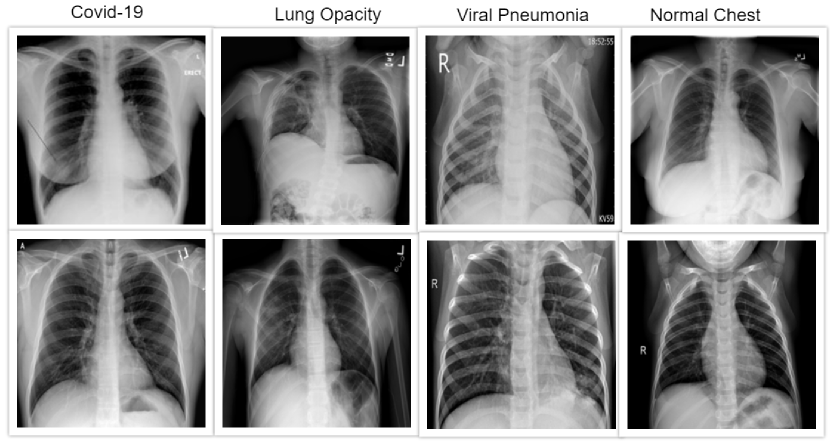

IV-A Dataset

The dataset selected in this study consists of samples from cases of COVID-19, lung opacity, viral Pneumonia, and healthy lungs. It was acquired from Kaggle, an online resource of open-source datasets[15][16]. The datasets consist of a total of 21,265 labelled X-ray images, of which 3,716 were COVID-19, 6,012 were lung opacity, 10,192 were viral Pneumonia, and 1,345 were normal lungs. We split the collected data into 70% for training, 10% for validation, and 20% for testing. Table III illustrates the dataset.